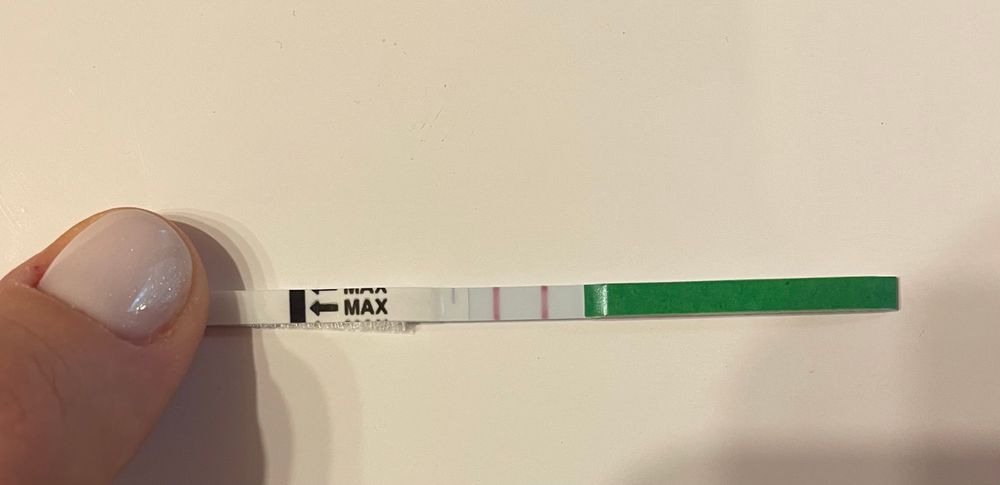

Это положительный на овуляцию?

Всем Привет!можно считать этот тест положительным?сегодня 19д.ц

Овуляция всегда поздняя.